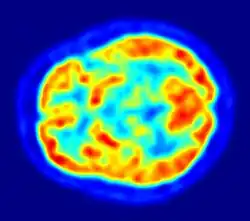

Although the human brain represents only 2% of the body weight, it receives 15% of the cardiac output, 20% of total body oxygen consumption, and 25% of total body glucose utilization.[138] The brain mostly uses glucose for energy, and deprivation of glucose, as can happen in hypoglycemia, can result in loss of consciousness.[139] The energy consumption of the brain does not vary greatly over time, but active regions of the cortex consume somewhat more energy than inactive regions, which forms the basis for the functional neuroimaging methods of PET and fMRI.[140] These techniques provide a three-dimensional image of metabolic activity.[141] A preliminary study showed that brain metabolic requirements in humans peak at about five years old.[142]